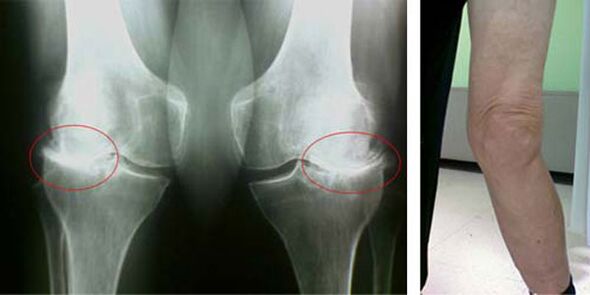

Šādas patoloģijas kā ceļa locītavas artrozes sākuma stadijas vizuāli nekādā veidā neizpaužas. Tomēr pēc noteikta laika pacients pamana ceļa deformācijas pazīmes, kā arī raksturīgu izliekumu gar apakšstilba asi (virzīts uz iekšu). Ir arī gurkstēšana, kad vajag saliekt kāju.

Sāpju klātbūtne, ierobežotas kustības ceļgalā liek cilvēkam vērsties pie ārsta un iziet pārbaudi. Lai to izdarītu, viņam ir jānokārto testi un jāveic slimās locītavas rentgens. Ja ar šiem pasākumiem nepietiek, lai apstiprinātu ceļa locītavas artrozi, tad tiek veikta magnētiskā rezonanse. Pamatojoties uz savāktajiem datiem, ārsts izvēlas labākās ārstēšanas metodes.